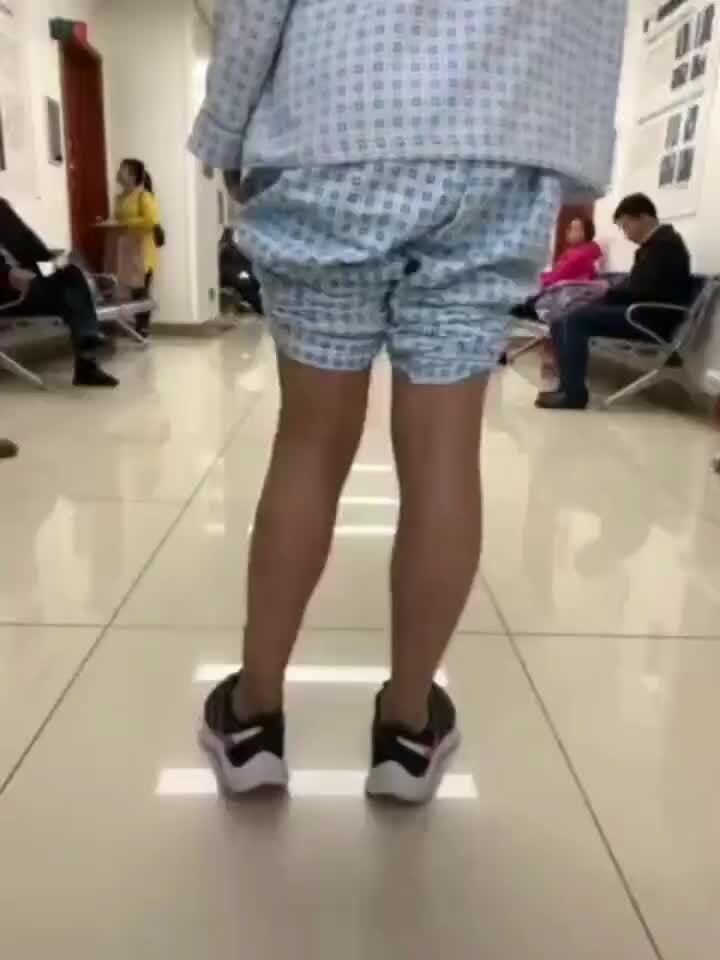

膝关节外翻正面观